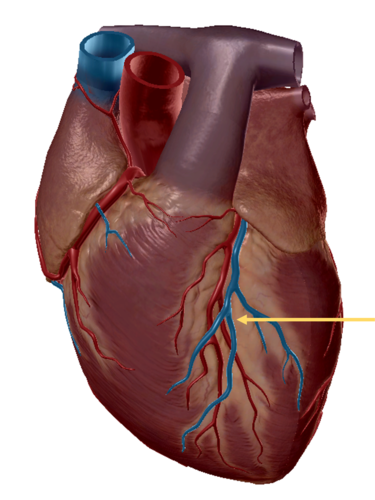

anterior inter ventricular sulcus

right coronary artery

circumflex artery

great cardiac vein

middle cardiac vein

anterior inter ventricular artery